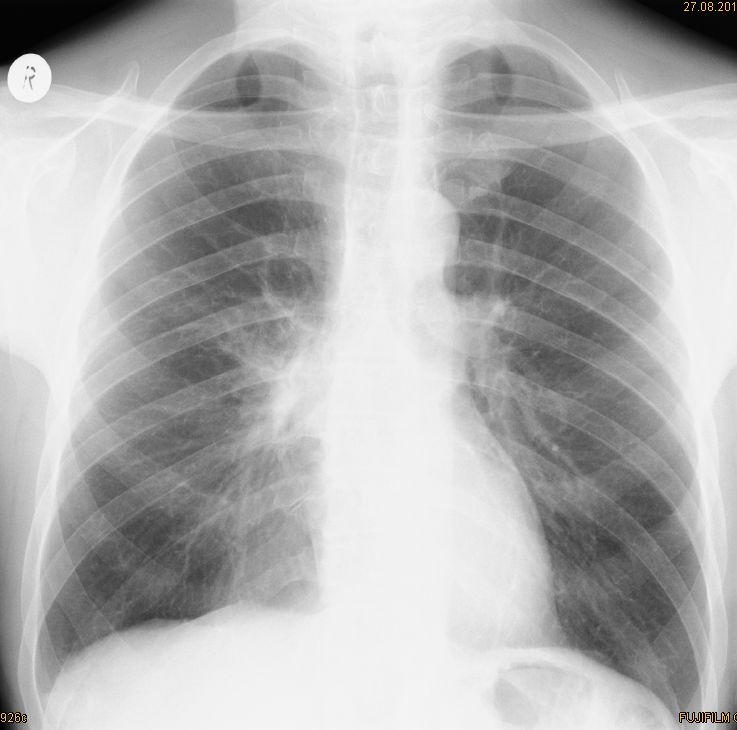

Röntgen Thorax Primärtumor im rechten unteren Unterlappen T2N3Mo. Nur diskrete Verdichtung im rechten unteren Hilus.